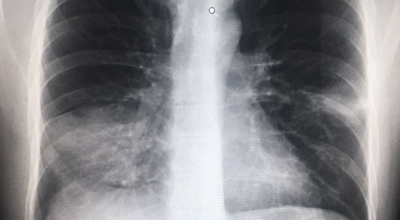

건강한 폐를 위해서는 폐의 활동을 유지하는데 도움을 주는 건강에 좋은 음식을 섭취해야 합니다. 폐는 우리 몸에서 중요한 역할을 하는 것은 말할 필요도 없어요. 그러나 결국 폐는 공기 뿐만 아니라 대기 오염과 담배 연기 같은 유해한 요소를 흡입하게 되는데요. 이런 오염 물질은 천식, 기관지염, 낭포성 섬유증 또는 폐렴등의 호흡기 건강 문제의 위험을 증가시켜요.

세계보건기구인 WHO 에 의하면 2억 3천5백만 명이 천식으로 고통 받고 있으며 이는 진단 또는 치료가 부족한 상태이지요. 그렇기 때문에 폐 건강을 향상시키기 위해서는 폐에 좋은 음식을 섭취할 필요가 있어요.